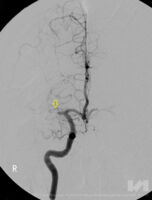

Hier besteht bei einem Teil der Patienten die Möglichkeit, das Blutgerinnsel mechanisch mittels eines Katheters - ähnlich dem Herzkatheter - zu entfernen: Das Gerinnsel wird direkt über ein Maschengitter (ein 4-6 mm großer sog. Stent) herausgezogen oder abgesaugt. „Katheter werden - innerhalb der ersten 6 Stunden nach dem Schlaganfall - mittels eines Microkatheters über die Leiste bis in das Gehirn des Patienten vorgeschoben, und zwar an jene Stelle, an welcher das Blutgerinnsel (Thrombus) die Schlagader im Hirn verstopft. Dort wird der Stent geöffnet, das Gerinnsel bleibt im feinen Metallnetz hängen und kann mittels Katheter herausgezogen und aus dem Körper entfernt werden (= Ektomie - Herausschneiden, Herausholen)“, führt der interventionelle Radiologe OA Dr. Thomas Haglmüller, Experte in der interventionellen Behandlung von Schlaganfällen, aus. Die Thrombektomie ist somit eine mechanische Methode, um die Gefäße zu eröffnen. Eine Behandlung kann zwischen 30 Minuten und 2 Stunden dauern. Dieses Vorgehen ist durch Studien bestätigt worden. Voraussetzungen, um eine Thrombektomie durchführen zu können, ist neben der Größe des Gerinnsels aber auch seine Lage: Die Therapie ist nur dann anwendbar, wenn das Gerinnsel die größeren Arterien im Gehirn verschließt - sie ist somit nicht für alle Hirnregionen geeignet. „Mit der Thrombektomie können wir große Gefäße im Gehirn schneller und vor allem effizienter eröffnen, um die Schädigung zu verringern“, erklärt Dr. Haglmüller. Seit 2 Jahren steht Schlaganfall-Patienten in Vorarlberg diese neue Behandlungsmethode zur Verfügung, insgesamt werden jährlich 40-50 Patienten mittels dieser Methode erfolgreich behandelt. Wichtig ist, dass die Betroffenen rechtzeitig bzw. ohne Verzögerung ins Zentrum gebracht werden. Nur so haben sie eine Chance!